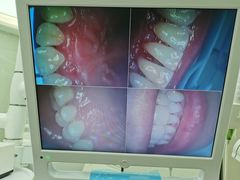

• -牙博士口腔品牌连锁(杨浦店)

点小评6520037363 | 21-12-12

报错